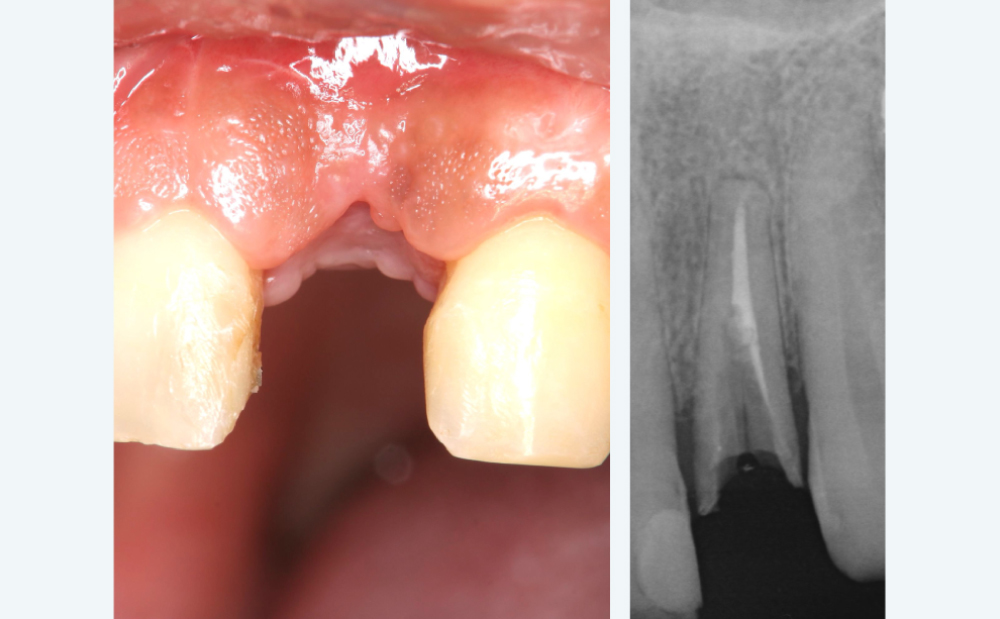

BEFORE

事故により前歯が破折。その後抜歯。

事故により前歯が破折。その後抜歯。

ブリッジだと削る量が多くなるため相談

ブリッジだと削る量が多くなるため相談

AFTER

違和感のない自然な前歯に

違和感のない自然な前歯に

自信を持って笑えるようになったと満足いただきました

自信を持って笑えるようになったと満足いただきました

| 治療内容 | 前歯1本のインプラント+ジルコニアクラウン |

|---|---|

| 治療期間 | 約6ヶ月 |

| 費用 | 約45万円(税込) |